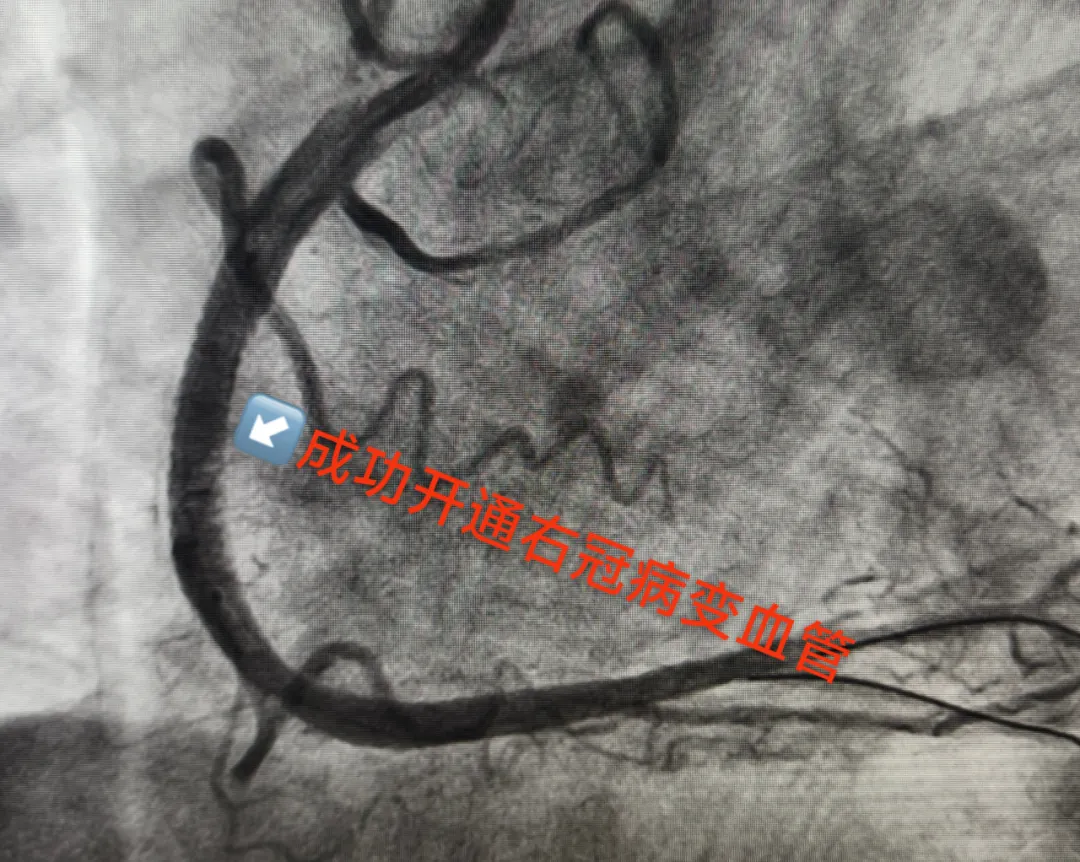

心内科团队接力:将造影导管送至冠状动脉开口,通过同一入路更换造影导管,造影剂注入瞬间,屏幕上清晰显示右冠状动脉中段一处近乎闭塞的狭窄–狭窄程度高达99%,如同心脏供血的“主干道”被掐住了喉咙!若不及时处理,随时可能引发急性心肌梗死甚至猝死。

精准植入支架:打通心脏“生命线”

面对冠脉的严重狭窄,手术团队当机立断:立即开通血管!凭借丰富的介入治疗经验,医生精准送入球囊扩张狭窄部位,随后植入一枚药物洗脱支架。随着支架完美贴合血管壁,原本几近闭塞的右冠状动脉血流瞬间恢复通畅,患者胸痛症状当场缓解,生命体征趋于平稳。